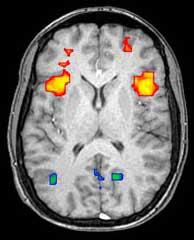

15:20 – Jeff: 乌尔姆大学的神经科医生 Michael Orth 研究大脑“默认模式网络”的变化。这些是大脑在我们“空闲”或“做白日梦”并且没有考虑特定事物时活跃的部分。当我们专注于某个特定事物时,这些脑区域通常会平静下来。在 HD 突变携带者的大脑中,这种平静是不完整的,原因尚不清楚。像 Michael Orth 这样的科学家使用一种称为“功能性磁共振成像”或 fMRI 的技术来研究大脑的哪些部分在给定时间处于活跃状态。

15:27 – Ed: Nellie Georgiou-Karistianis(澳大利亚)也在谈论大脑活动。G-K 博士在功能性 MRI 扫描仪中使用思维测试来挑战和探测亨廷顿病突变携带者的大脑功能。她正在随着时间的推移重复使用 fMRI,我们可以看到 HD 的变化以及我们可以测量的内容,并旨在通过治疗来挽救。